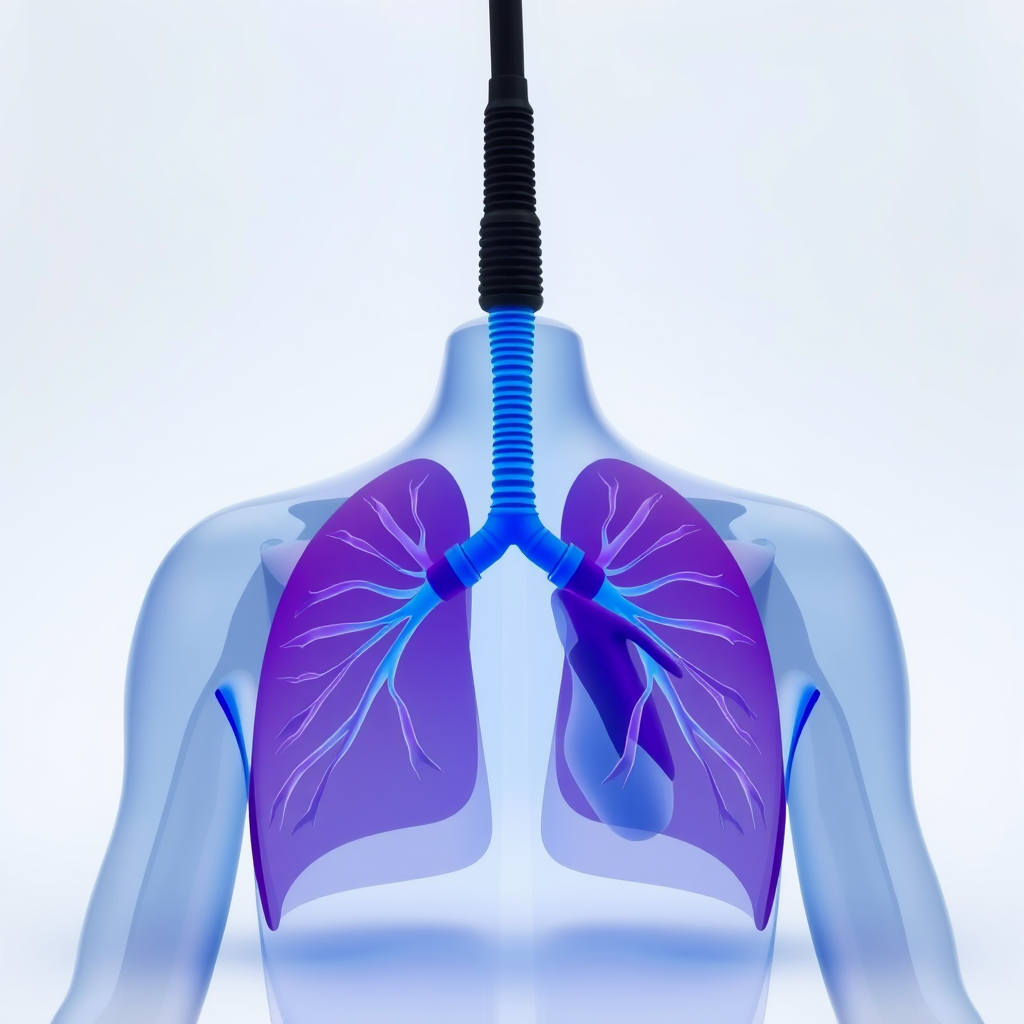

Esse tipo de fisioterapia é essencial para a recuperação e manutenção da saúde respiratória e cardiovascular.

A fisioterapia cardiorrespiratória é indicada para pessoas que passaram por cirurgias cardíacas, possuem doenças pulmonares ou desejam melhorar a capacidade física.

Melhora da capacidade pulmonar e respiratória

Um dos principais benefícios da fisioterapia cardiorrespiratória é a melhora da função pulmonar.